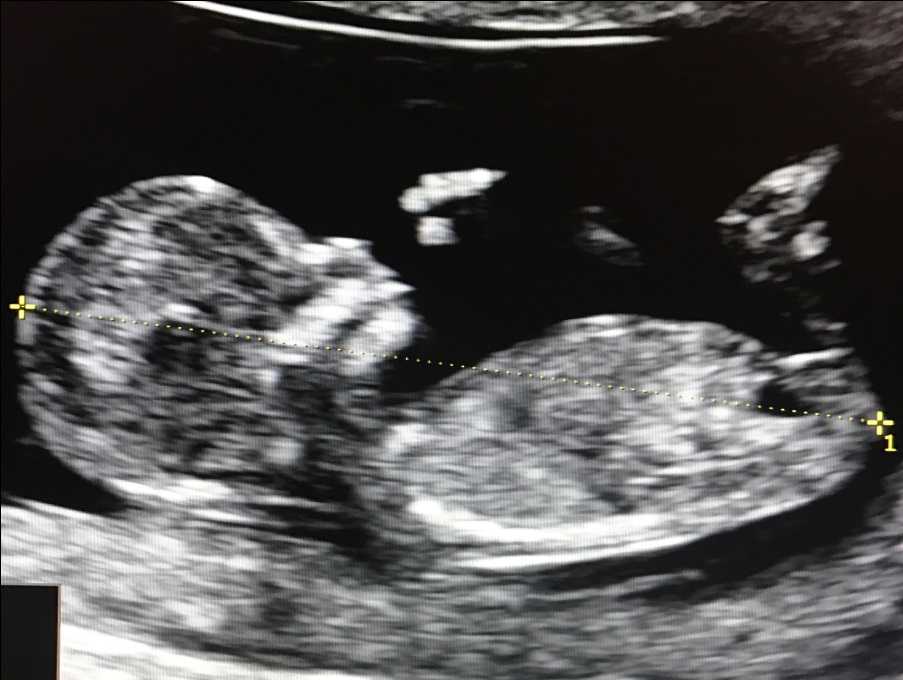

Признаки синдрома Дауна при узи во втором триместре беременности

При проведении узи плода во втором триместре беременности можно обнаружить такие отклонения как нарушение формирования костей скелета, расширение воротникового пространства более, чем на 5 мм, наличие пороков сердца, расширение почечных лоханок (пиелоэктазия), эхогенность кишечника, кисты сосудистого сплетения головного мозга. Причем только пороки сердца, нарушения формирования скелета и расширение воротникового пространства являются независимыми факторами риска.

Установление риска синдрома Дауна у плода на УЗИ называют ультразвуковым скринингом. Часто метод используется в комплексе с биохимическим анализом крови матери. Точность диагностики синдрома Дауна на УЗИ во втором триместре беременности может достигать 91%. Обследование проводится на 11-13 и 16-18 неделе беременности.

Что представляет собой скрининг во втором триместре беременности

Согласно приказу № 572н от 1.11.2012 г., второй скрининг состоит из ультразвукового исследования плода на сроке 18-21 неделя беременности. В этом возрасте кровь на биохимические маркеры уже не сдается. Плод имеет массу около 300-500 грамм и длину 20-25 см, и УЗИ позволяет детально проанализировать все анатомические структуры плода и выявить большинство пороков развития. Тогда же оценивается количество околоплодных вод, расположение и структура плаценты, длина шейки матки и др.